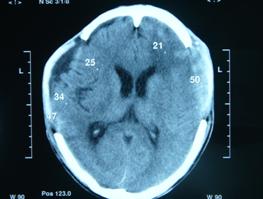

1.CT、MRIDSA檢查、常無明顯異常;也可表現為眶內軟組織腫脹。